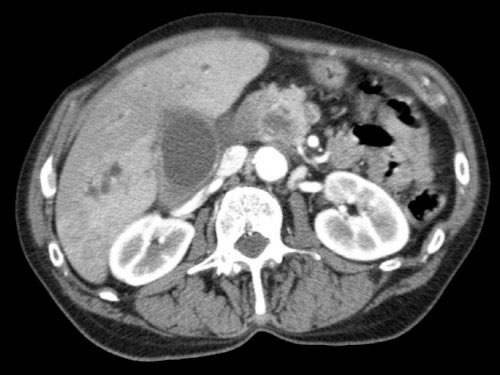

Đánh giá giai đoạn tại chỗ cần được thực hiện bằng CT tụy chất lượng cao, bao gồm thì động mạch muộn và thì tĩnh mạch cửa.

Ung thư biểu mô tuyến tụy thường biểu hiện là một khối giảm tỷ trọng, kém mạch máu, được nhận thấy rõ nhất ở thì động mạch muộn. Đây cũng là thì tốt nhất để đánh giá giải phẫu động mạch nhằm phát hiện các biến thể và hẹp mạch.

Thì tĩnh mạch cửa là tốt nhất để phát hiện di căn gan cũng như phát hiện hẹp và xâm lấn tĩnh mạch.